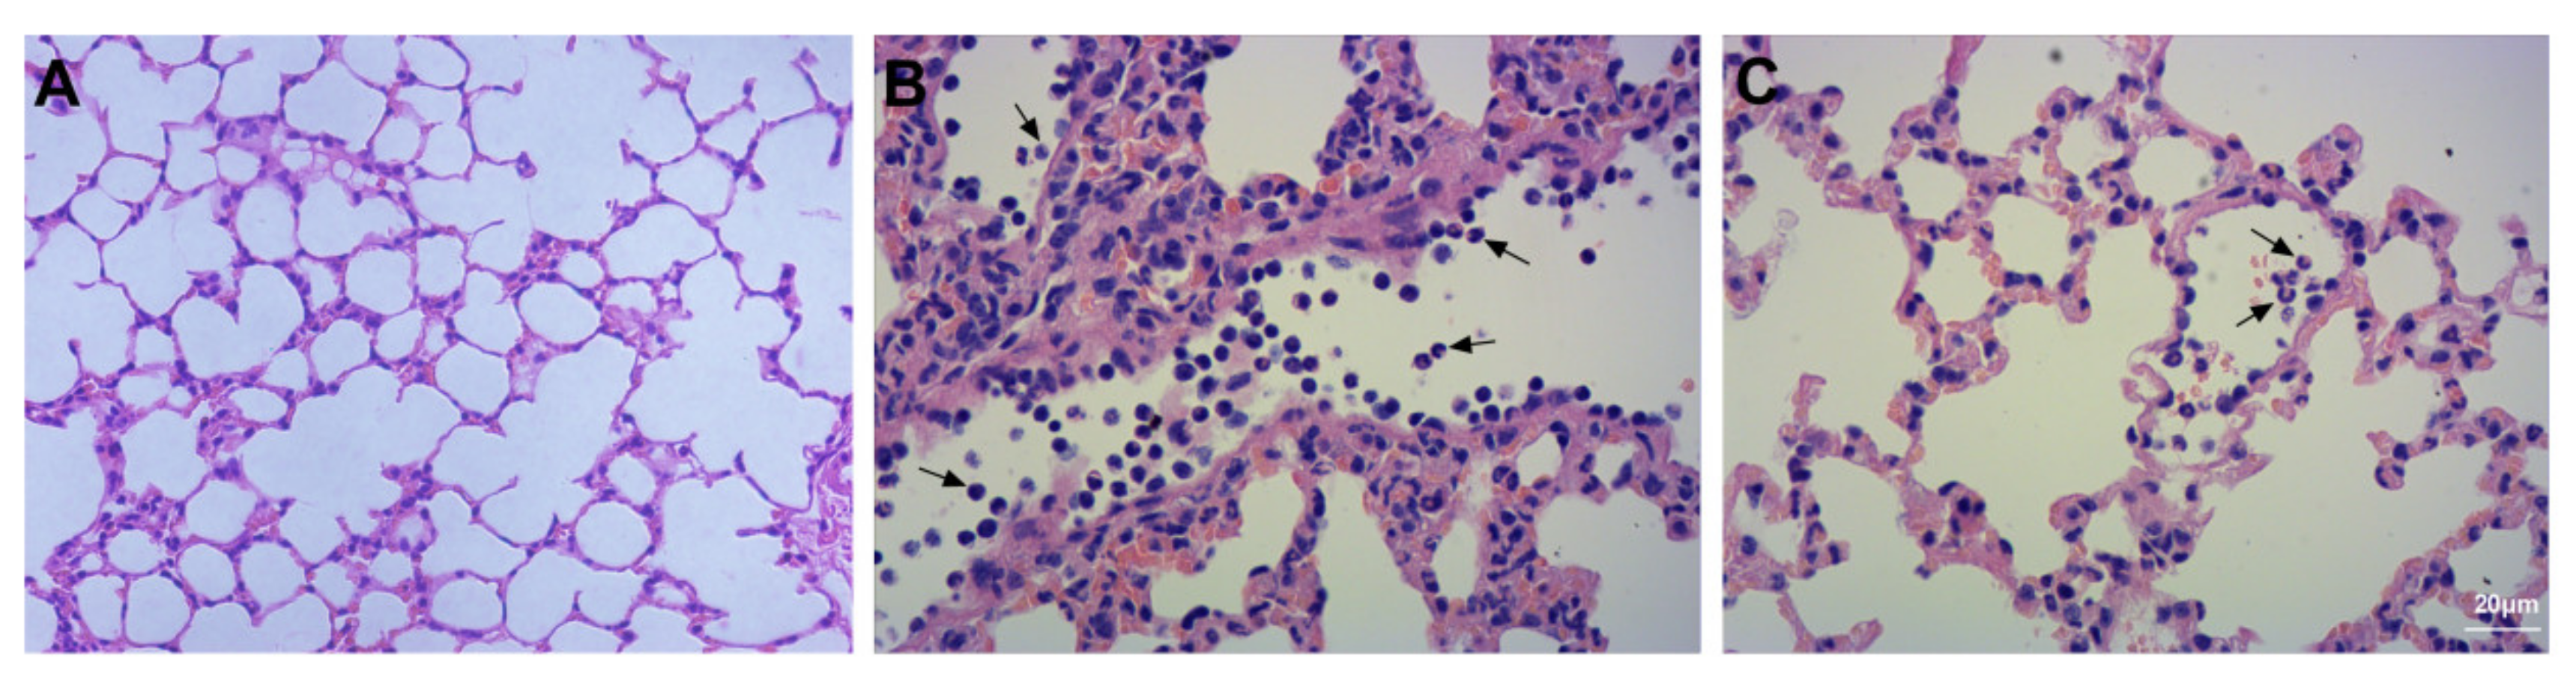

3.2. Assessment of Lung Injury and Neutrophil Infiltration